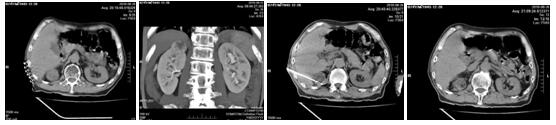

化療后病人一般情況尚可,經(jīng)過充分的術(shù)前檢查及準(zhǔn)備后,2018年6月26日在苗滿園主任的帶領(lǐng)下,與CT室聯(lián)合進(jìn)行手術(shù),局麻后在CT引導(dǎo)下將電極針準(zhǔn)確插入腫瘤內(nèi)部,對(duì)腫瘤實(shí)施微波消融術(shù)。僅20分鐘順利完成手術(shù),達(dá)到了預(yù)期的滿意效果和消融范圍。術(shù)中患者清醒無不適,術(shù)后6個(gè)小時(shí)患者即可下床活動(dòng)。術(shù)后評(píng)估微波消融治療范圍,無出血及鄰近臟器損傷。